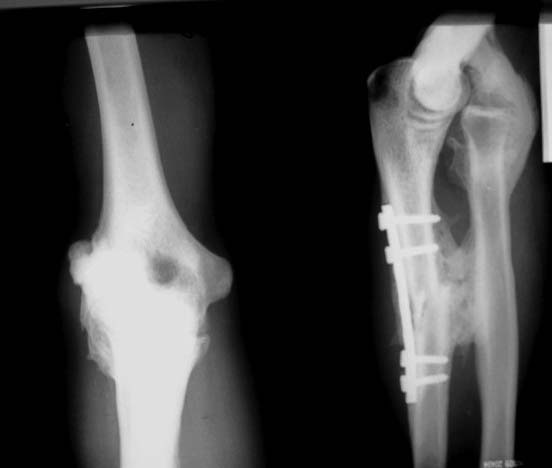

Добрый день. Интересно ваше мнение, уважаемые коллеги.

Мужчина 27 лет, травма год назад - удар по предплечью электропоездом.В ЦРБ - остеосинтез

локтевой кости, вероятно - открытое вправление вывиха головки лучевой кости (выписки нет,

но пациент говорит, что были металлические спицы и есть п/операционный рубец в проекции

головки лучевой кости). В настоящее время: движения в локтевом суставе отсутствуют.

предплечье находится в положении сгибания 160*. Хочется услышать мнения об объеме

оперативного вмешательства, во сколько этапов его проводить.